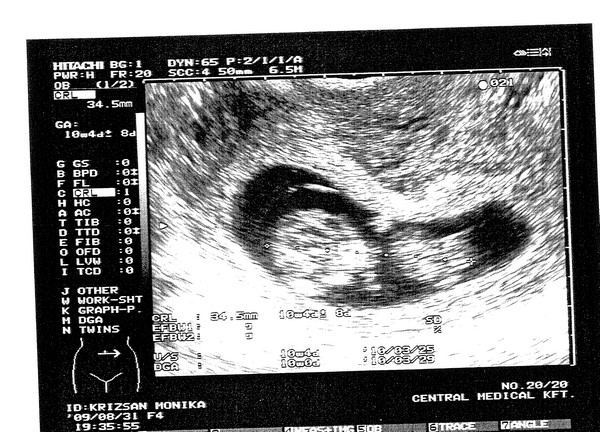

Ma voltam Timmermann dokinál, szimpinek tűnt, azt mondta, h betöltött 9 hetes vagyok, CRL: 21 mm és mindent rendben talált, 3 hét múlva kell mennem újra! :D

Jajj csajok, nagyon boldog vagyok, tegnap láttam a manócskát, 33 mm popsitól fejbúbig és már nagyon olyan, mint egy kisbaba! Hihetetlen volt! :D :D :D És nagyon aktív, össze-vissza kalimpált, meg lubickolt, igazi kis búvár! :D Őszintén szólva nagyon meghatódtam!

Na hát tegnap voltunk UH-n. Minden Ok!!! :) 34,5 mm a CRL.

Először csak nézegettük, meg a szívhangját hallgattuk, aztán a végén beindult a Babó. Úgy el kezdett ficánkolni, meg boxolni...apjával csak ámultunk, meg könnyeztünk. Szuper volt látni!

Na jó, akkor én is dicsekszem a pocaklakóm sztárfotójával... :lol:

Kép [/img]